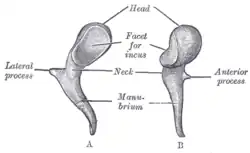

Ossículos

Ossículos Cabeça e pescoço de um embrião humano com dezoito semanas de idade, com cartilagem de Meckel e osso hióide expostos.